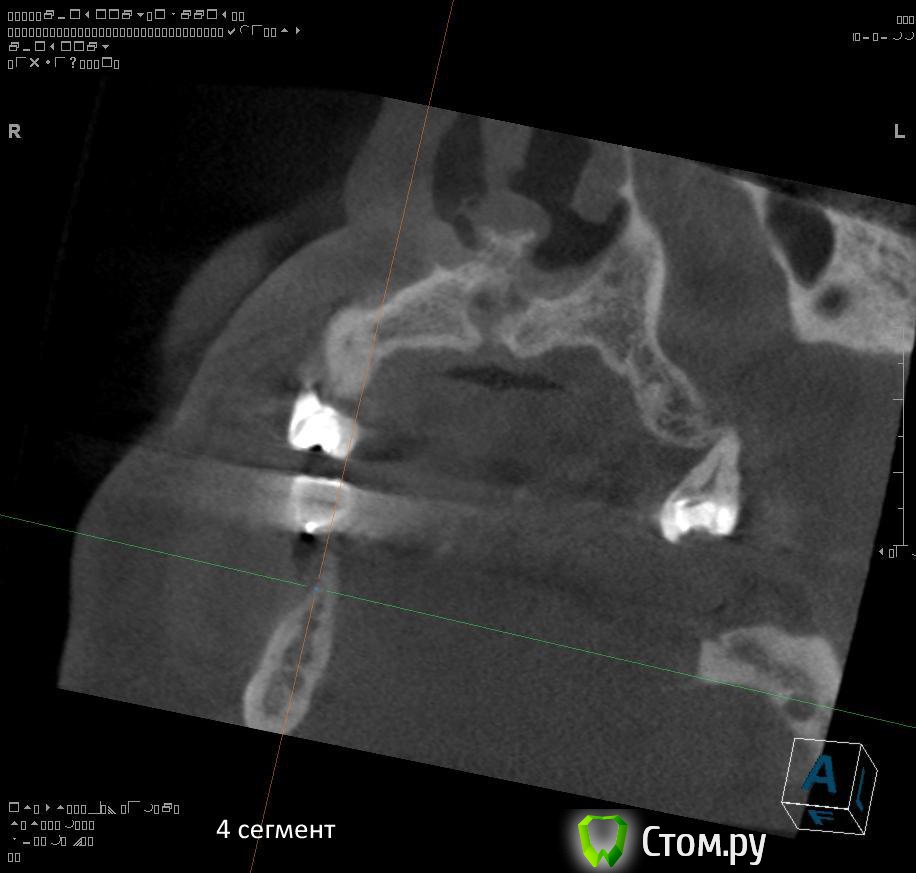

4. через 1,5 - 2 месяца после удаления 4.4 и 4.7 провести установку имплантатов в 4 сегменте?

5. в какие позиции должны быть поставлены имплантаты в 4 сегменте сбоку (4.5, 4.7?)?